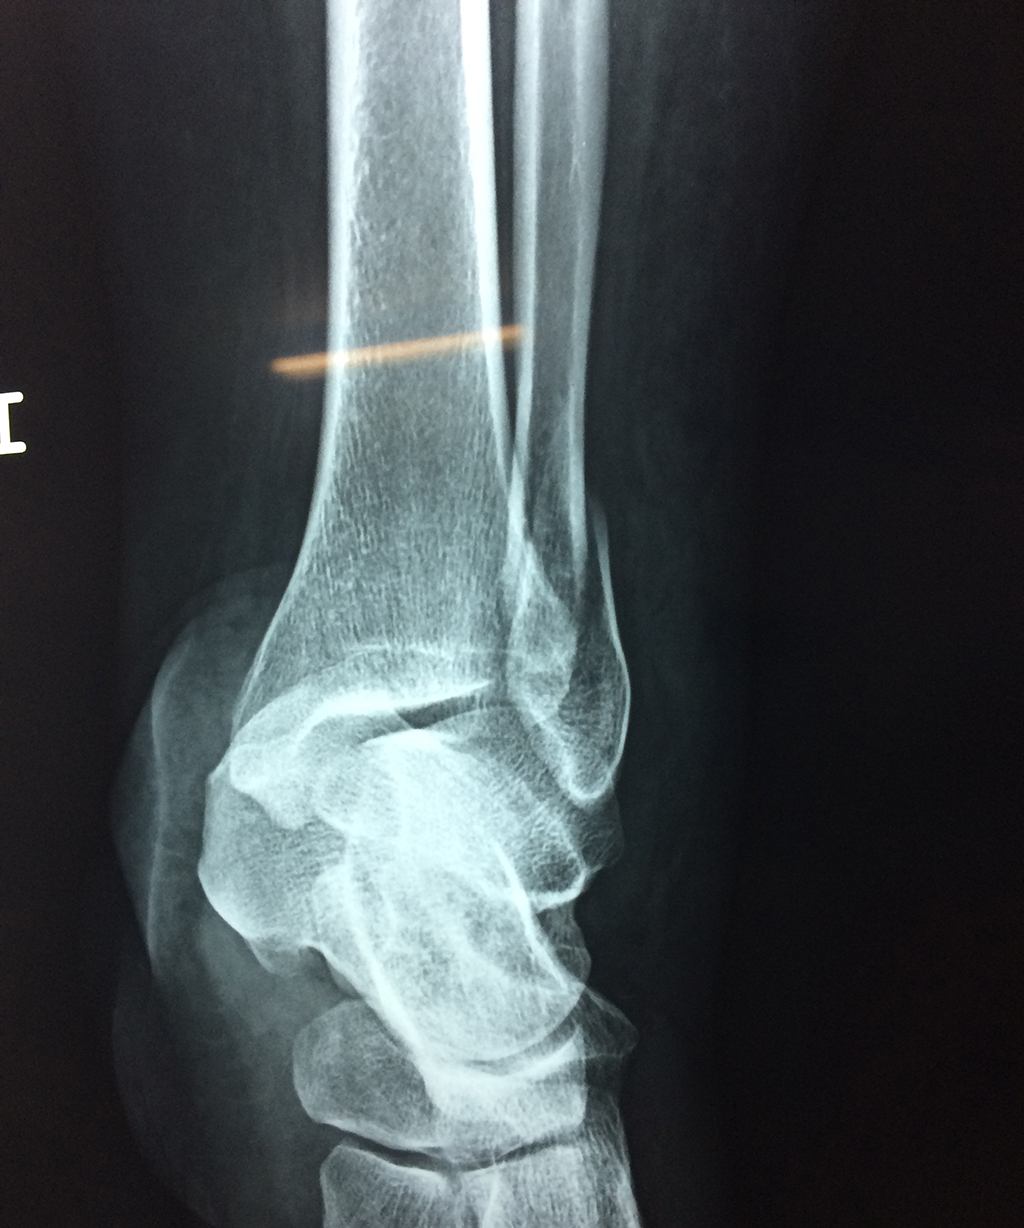

Una fractura de tobillo es la rotura de uno o más de los huesos del tobillo. Estas fracturas pueden ser:

Algunas fracturas de tobillo pueden requerir cirugía si:

- Los extremos de los huesos están desalineados entre sí (desplazados).

- La fractura se extiende hasta la articulación del tobillo (fractura intra-articular).